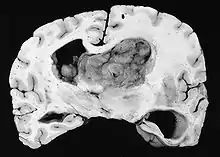

Photograph of a brain section containing a subependymal giant cell astrocytoma

A NIH Consensus Conference report in 1999 recommends that any SEGA that is growing or causing symptoms should be surgically removed.[2] Tumors are also removed in cases where a patient is suffering from a high seizure burden.[1] If a tumor is rapidly growing or causing symptoms of hydrocephalus, deferring surgery may lead to vision loss, need for ventricular shunt, and ultimately death. Total removal of the tumor is curative.